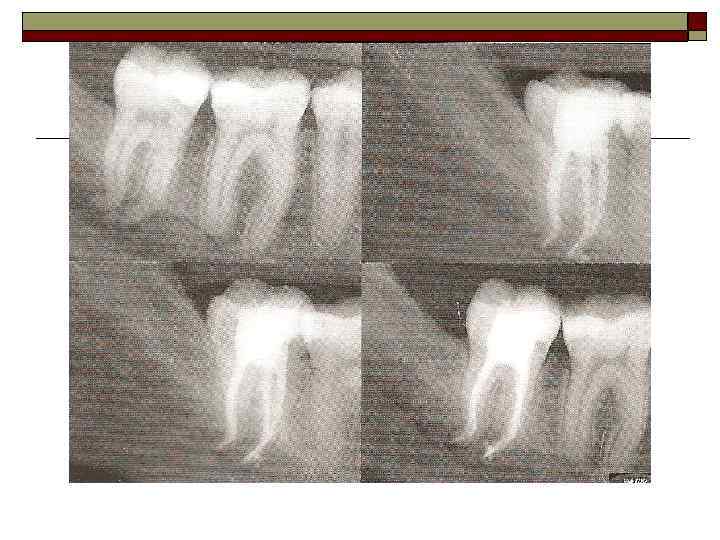

II. Пародонтит — воспаление тканей пародонта, характеризующееся прогрессирующей деструкцией периодонта и кости. Тяжесть: легкая, средняя, тяжелая. Течение: острое, хроническое, обострение (в том числе абсцедирование), ремиссия. Распространенность процесса: локализованный, генерализованный.